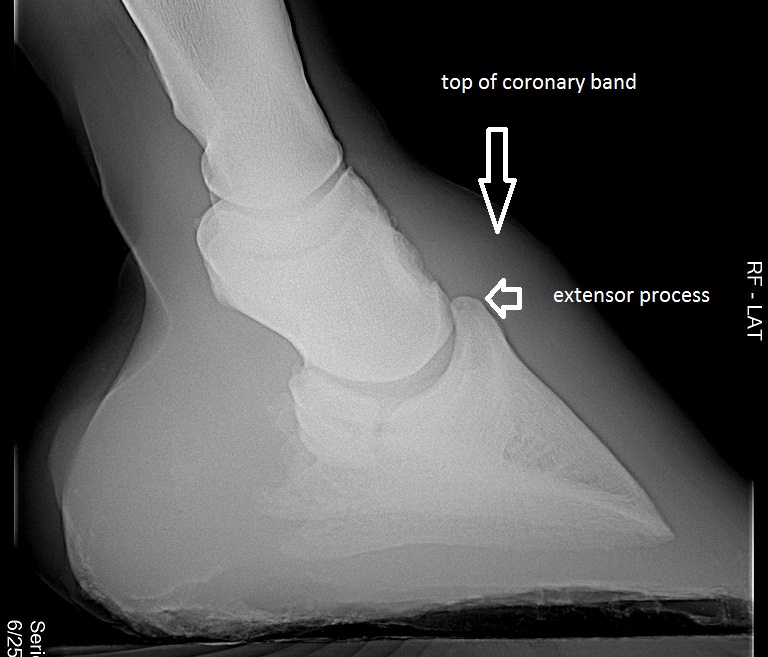

Given the consistency in height of the coffin bone, we can conclude that too long and/or too tall a hoof capsule cannot be a sign of good health, and we can train our eye quite quickly to this factor. There is however still the variant of how high within the hoof capsule the coffin bone is placed. Usually, the very top of the coffin bone, the extensor process, sits about 6 to 8 mm below the top of the coronary band. In wild horses, it is placed often higher, allowing for a shorter hoof capsule. In diseased hooves, it is often placed lower, a condition that is called “ too much distal descent” of the coffin bone. (Pete Ramey wrote a wonderful article about that. Go to this link http://www.hoofrehab.com/jessica.htm for reading.)

Fig. 37 shows a radiograph of a hoof.

This coffin bone seems in an appropriate position height-wise, although it is hard to tell because the coronary band is not clearly marked in this picture. Most veterinarians fail to do that.

Fig. 37